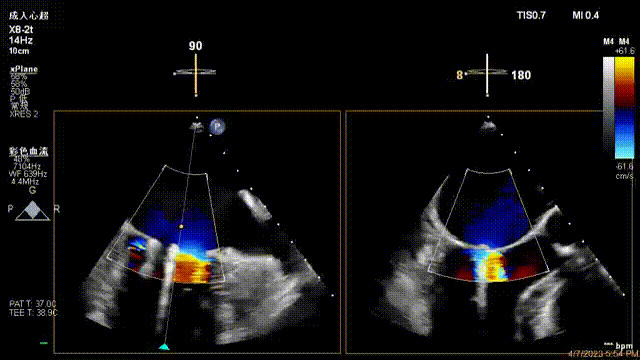

接受治療的是一例器質(zhì)性重度二尖瓣反流(DMR)患者,主訴“反復(fù)活動后胸悶,氣促3年余”。術(shù)前超聲顯示,雙房增大,二尖瓣脫垂伴重度反流,輕度三尖瓣反流,輕度肺高壓,升主動脈增寬。手術(shù)經(jīng)股靜脈-房間隔入路,采用全身麻醉插管,在TEE和DSA引導(dǎo)下完成房間隔穿刺。置入JensClip瓣膜夾系統(tǒng)后,在左房調(diào)整瓣膜夾的位置和軸向,后進入左室,在TEE引導(dǎo)下捕捉二尖瓣前后瓣葉,并關(guān)閉瓣膜夾。經(jīng)TEE反復(fù)確認手術(shù)效果后最終鎖定并釋放瓣膜夾。術(shù)后即刻超聲顯示瓣膜夾位置穩(wěn)定,功能良好,術(shù)前二尖瓣反流4+,術(shù)后0反流,肺靜脈逆流和左房壓都顯著好轉(zhuǎn),手術(shù)圓滿成功(以上數(shù)據(jù)都來源于醫(yī)院的臨床記錄)。術(shù)后患者狀態(tài)良好,目前已安排出院。

術(shù)后超聲顯示二尖瓣反流消失,瓣膜夾穩(wěn)定